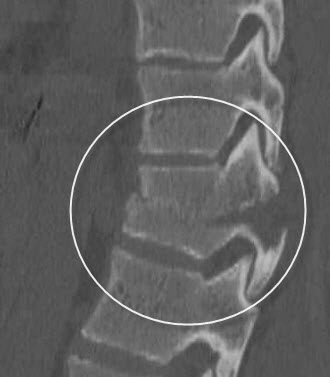

compression fx

collapse of body from osteoporosis, kyphosis, trauma, or pathologic disease. Anterior wedge collapses, changing the shape to a wedge, best demoed on a lateral spine